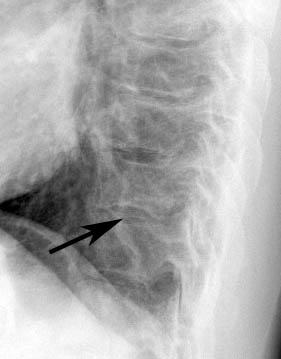

Congenital

Sickle Cell 1 Lat c/u